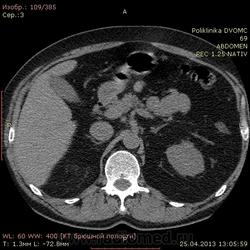

Уважаемые коллеги КТ-шники 2 часа ищу холедох, все перерыл, пересравнивал. Четко его так и не нашел, а в книжках пишут(можт обманывают?), что должен быть виден всегда. В сязи с этим огромная просьба: помогите!!!! и ткните, наконец, стрелкой в то место куда надо смотреть...спасибо.

Ткнуть, говорите? Это можно. Вспоминаем анатомию: гепатиколедох расположен в печеночно-двенадцатиперстной сваязке кпереди от воротной вены.